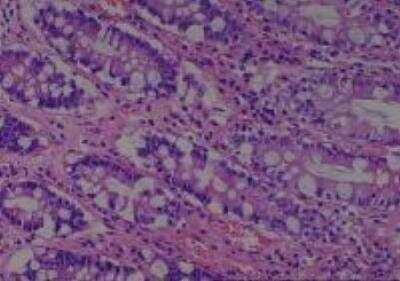

Scientific Data Images for Human Multi Tissue MicroArray (Normal Adjacent)

Hematoxylin & Eosin Stain: Human Common Tissue MicroArray (Normal Adjacent) [NBP2-30215] - 102. Stomach